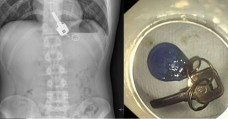

Kebingungan Cari Kunci yang Hilang, Pria Ini Ternyata Tak Sadar Menelannya